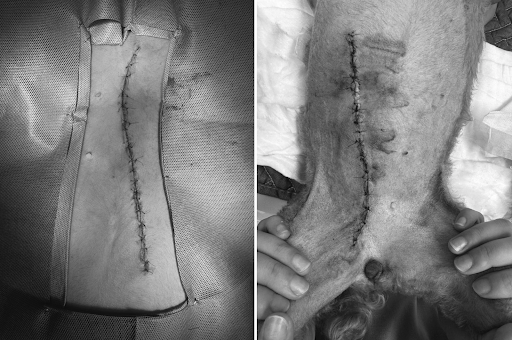

13살의 고령이었지만, 심장 초음파·혈액검사·흉부 방사선 등 사전 평가를 철저히 진행한 후 안전한 전신마취 하에 수술이 진행되었습니다.

유선종양 수술사진 / 출처: 24시온숲동물의료센터

제거된 종양 사진 / 출처: 24시온숲동물의료센터

수술은 출혈 없이 안정적으로 마무리되었으며, 종양과 주변 조직이 완전히 제거되었습니다.

제거된 종양은 병리조직검사를 위해 의뢰하였습니다.

수술 후 환자는 온숲 의료진의 세심한 입원 관리 아래 수액치료, 통증 조절, 항생제 치료를 병행하여 안정적으로 회복 후 퇴원했습니다.